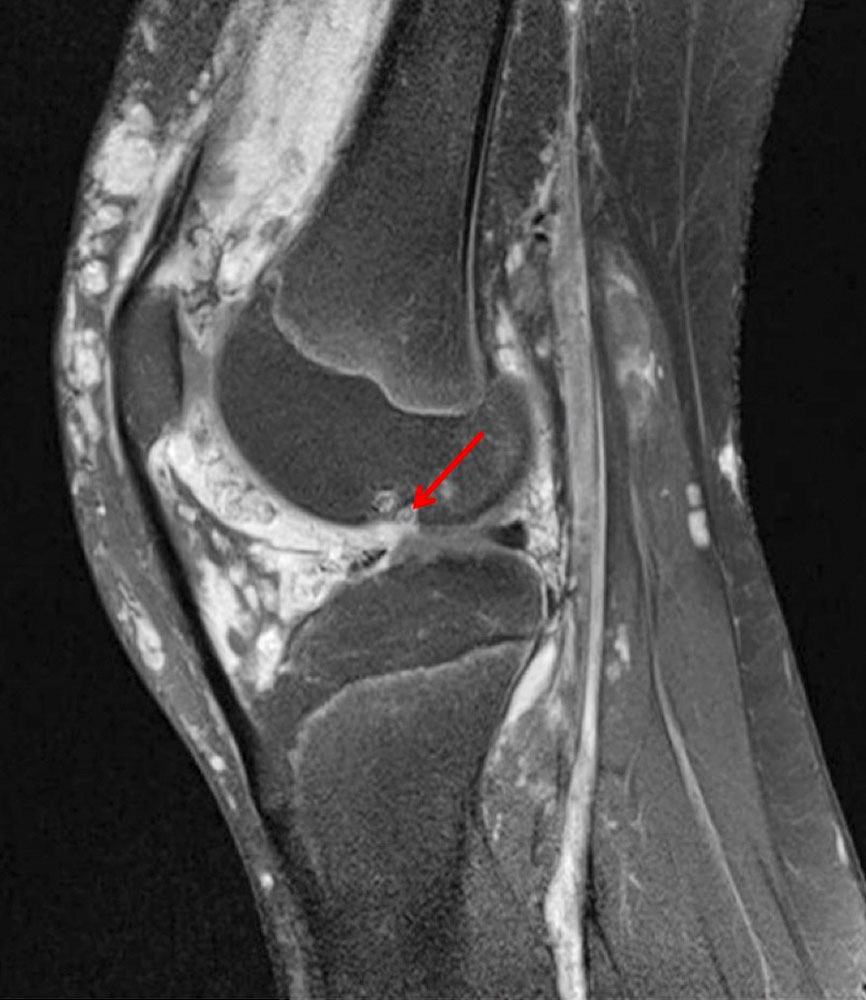

MRI then plays an essential role as a further diagnostic tool, as it can be used to assess a possible intra-articular extension of the malformation and to detect hemosiderin residues in the synovium in iron-sensitive sequences in a condition following direct bleeding in the joint.

The diagnosis of angiodysplastic arthropathy is based on the patient's medical history. It is important to ask whether the patient with vascular malformation has ever (or repeatedly) experienced joint effusion or recurrent inflammation, especially in the knee joint. If the answer is positive, it can be assumed that hemarthrosis or thrombophlebitis close to the knee joint with synovial involvement has occurred.

Although this disease has not yet been sufficiently researched in detail, the further course can be predicted by considering other diseases that lead to repeated bleeding or an inflammatory co-reaction in joints (e.g., blood coagulation disorders). Triggered by an inflammatory co-reaction of the synovium in the case of venous malformations directly close to or in the synovium with recurrent thrombophlebitis, rapidly progressive destruction of the joint on the affected side already occurs at a young age.